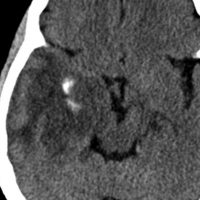

何と言っても診断的価値があるのは 石灰化 carcification です。左のCTの中央にみえる白い部分が石灰化です。この程度の石灰化でも診断的な価値があります。1p/19q codeletionがあるオリゴでした。病理では,均一な小型の円形核を有する細胞と多数の毛細血管 chickin-wire network がみられます。部分摘出後,放射線治療とテモゾロマイド化学療法でコントロールできています。

極めて高度な石灰化:脳石 brain stone

左は通常のCT,右は骨条件CTです。左前頭葉に巨大な石灰化を伴う乏突起膠腫があります。病理組織像は基本的にはグレード2です。石の塊のようにみえるので braine stoneと呼ばれ,CT eraでは oligodendrogliomaの hallmarkと言われました。